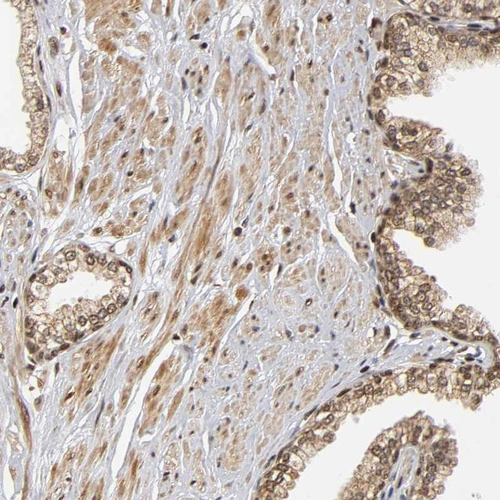

Immunohistochemical staining of human Fallopian tube shows strong nuclear positivity in glandular cells.